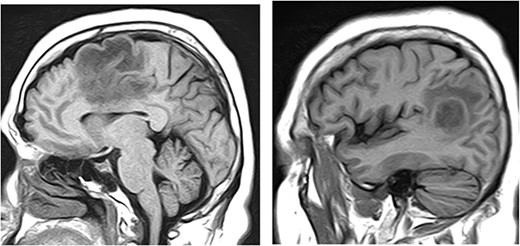

The MRI of brain without contrast showed two enhancing masses in the left frontal and left parieto-occipital lobes (Fig. 4), 2.1 cm × 2.7 cm × 1.9 cm and 1.9 cm × 2.0 cm × 2.5 cm, respectively. These were interpreted as possibly representing the adjacent satellite lesions. There was extensive surrounding vasogenic edema, causing approximately 3 mm of the left to right midline shift. These enhancing left frontal and left parieto-occipital masses were interpreted as being compatible with brain metastases.

MRI of brain without contrast showed two enhancing masses in the left frontal and left parieto-occipital lobes, 2.1 cm × 2.7 cm × 1.9 cm and 1.9 cm × 2.0 cm × 2.5 cm, respectively.